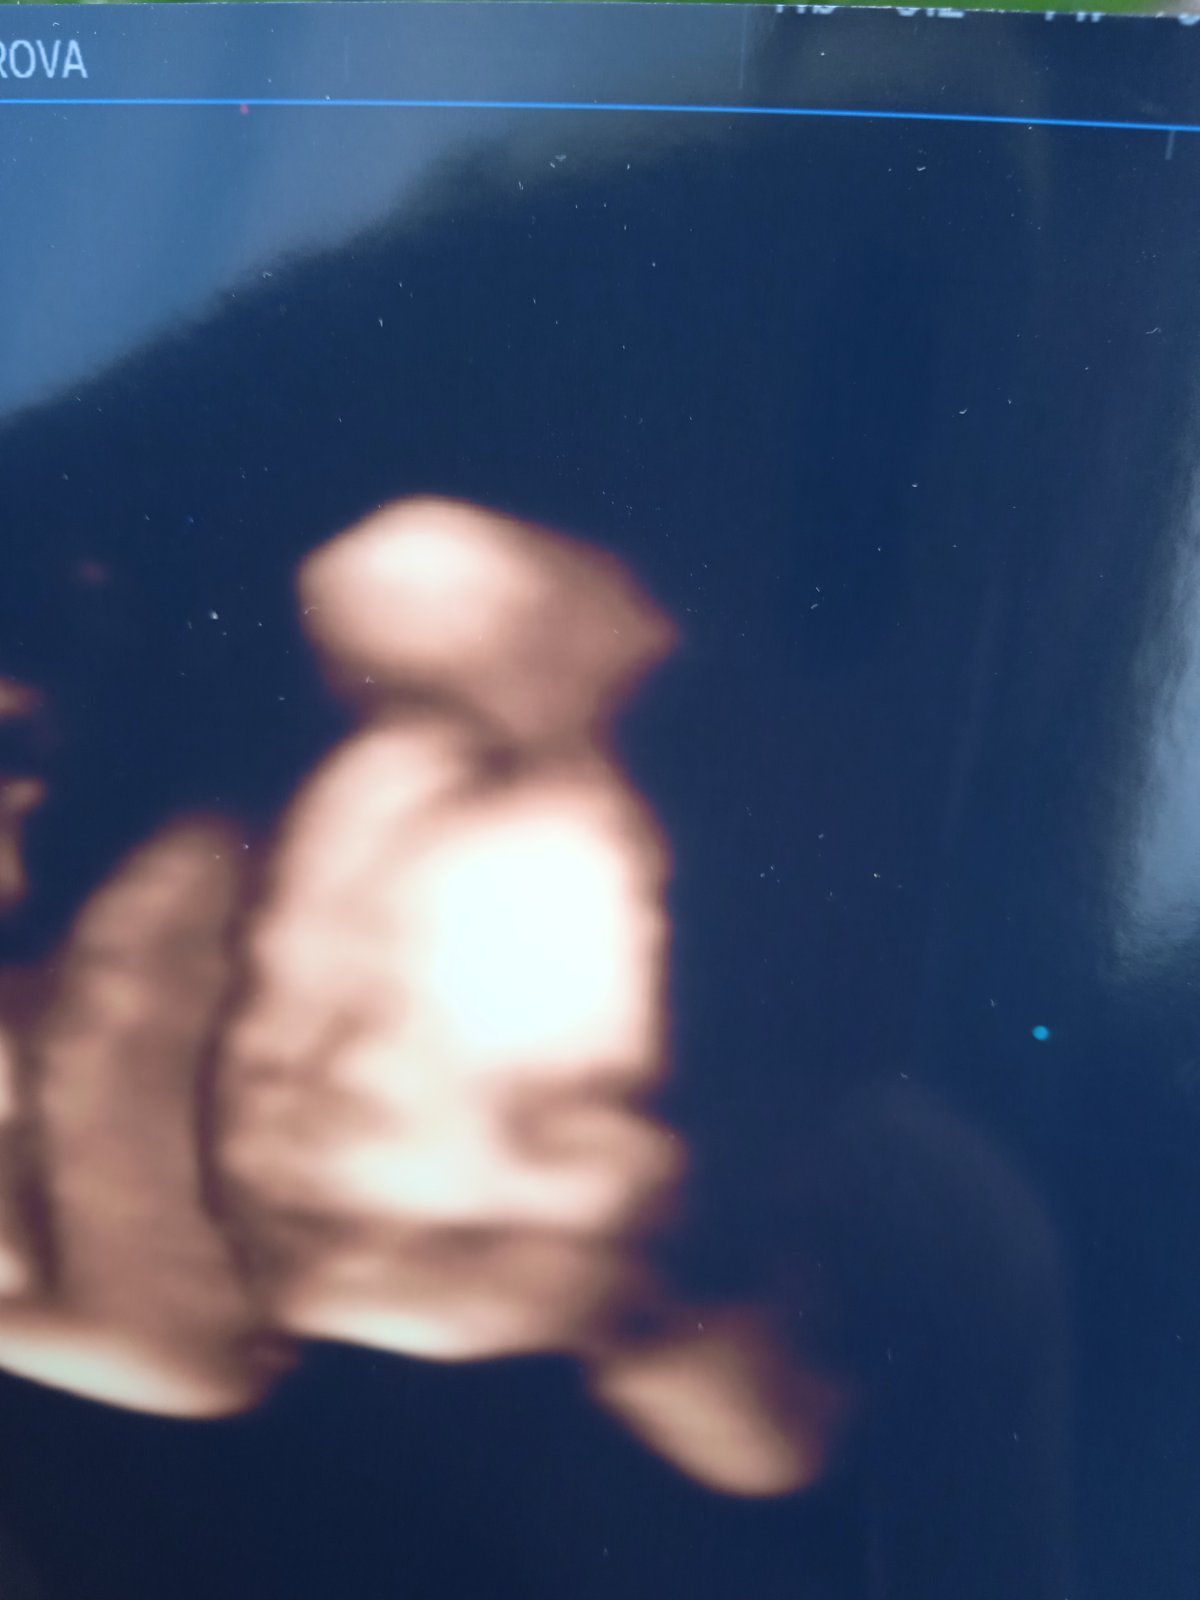

@anickaaa28 Tak moc držím pěsti. Já mám konečně fotečku obličeje malé, sice kvalita nic moc, ale byla jsem úplně unesena z toho, jak se směje. Už teď ji moc moc miluju.

@veroveru Ja chci taky pak takovou fotku ale doporučila mi sestra počkat do toho 28 tydne,ze to miminko pak vypadá uz jinak.U mladšího syna jsem sla driv a nic moc i když hezká je.Je to zlaté

@anickaaa28 děkuji. No pořád kluk kluk a na té genetice že holka a na dalším ultrazvuku potvrzena❤️ taky zkusím ještě v tom 28tt poprosit o jednu fotku. Uvidíme. Ale z toho jak se malá směje jsem byla totálně ko úplně hotová. Proto jsem ji chtěla i když není až tak kvalitní 😁 proč jdeš na tu štítnou zlazu?